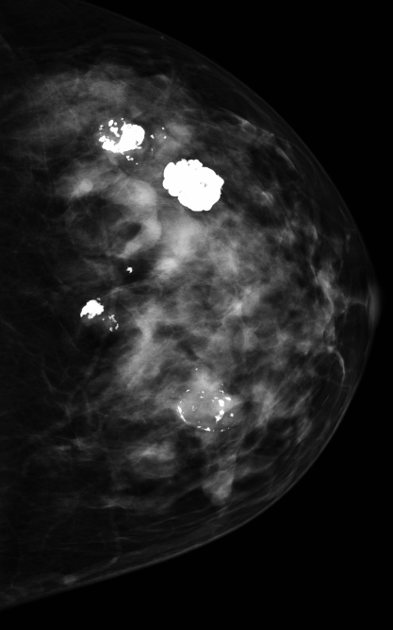

DIagnosis?

Popcorn calcs in a degenerating fibroadenoma.